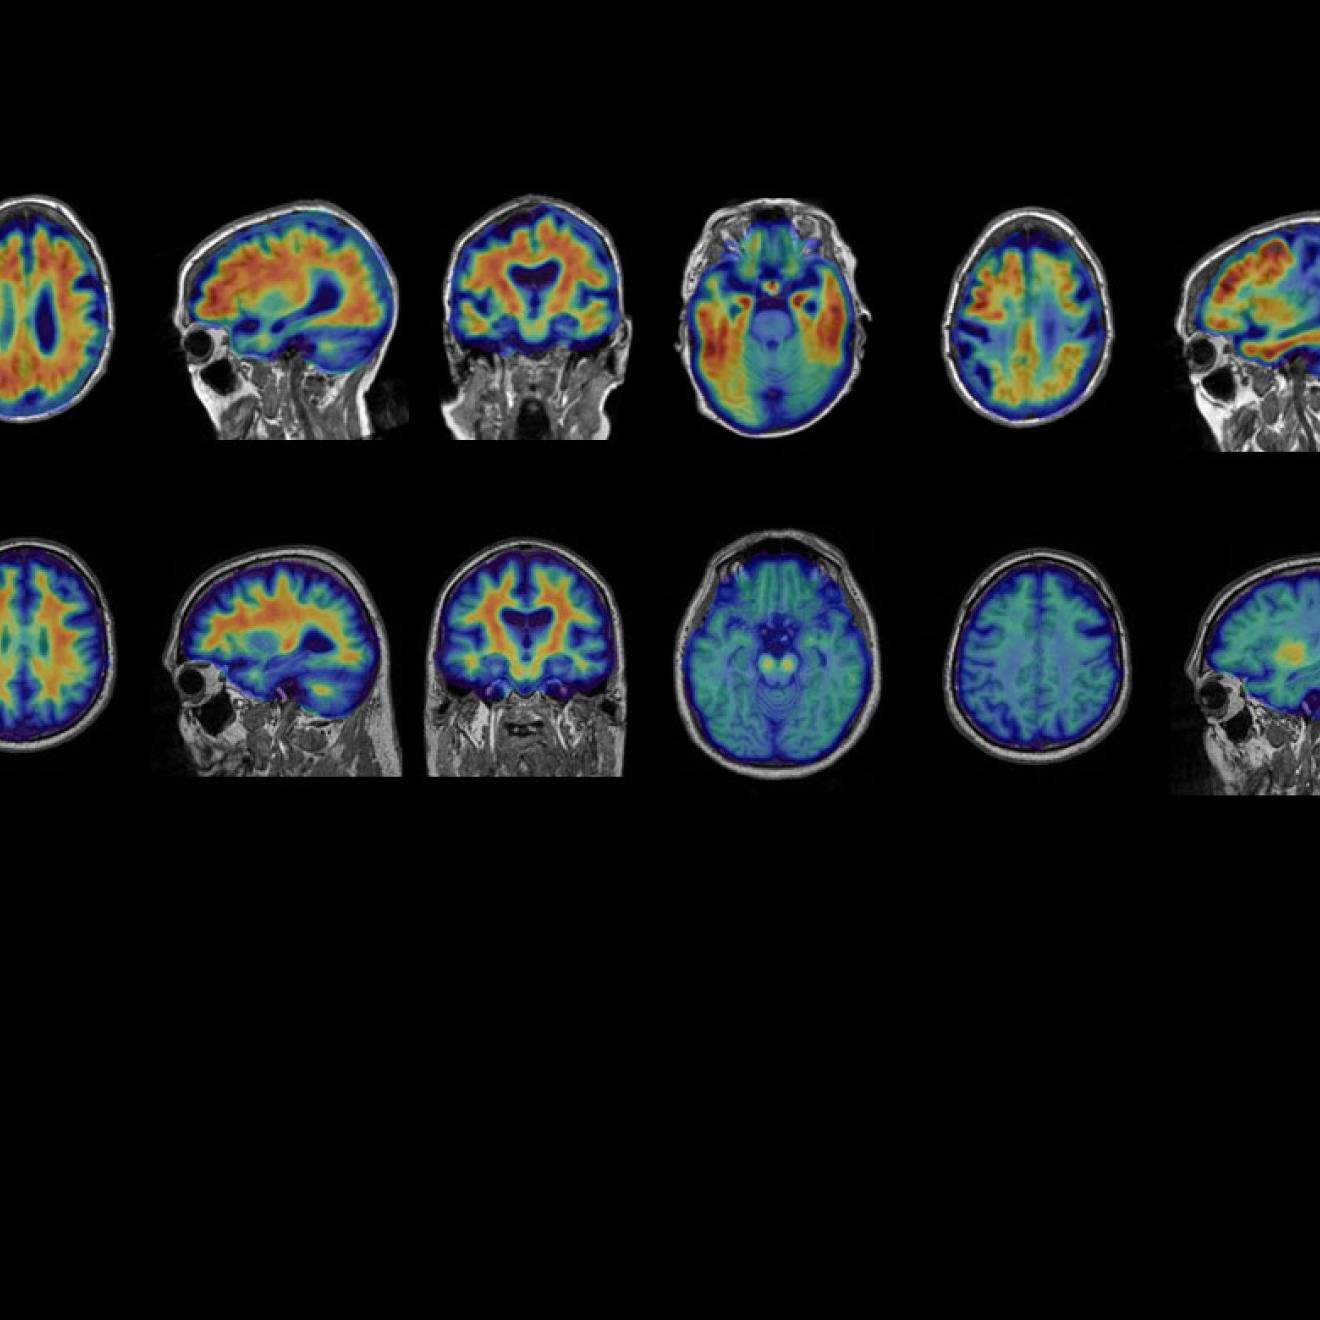

Lincoln has used high-powered neural imaging to gain a better understanding of sleep’s role in a brain clearance process thought to be linked to Alzheimer’s. There are higher rates of the disease in Black communities, and researchers believe sleep disturbance plays a role.